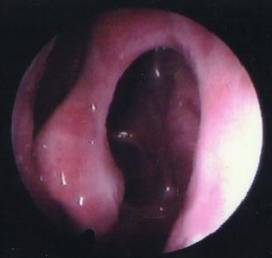

1、内镜检查:来源于中鼻道、嗅裂的黏脓性分泌物,中鼻道粘膜充血、水肿或有鼻息肉。

- 鼻腔检查:前鼻镜、鼻内窥镜。

① 病情完全控制:症状完全消退、VAS总评分0分,手术后鼻内镜检查窦口开放良好,窦腔粘膜开放良好,窦腔粘膜水肿消失,无粘性或黏脓性分泌物,上皮化良好。

② 病情部分控制:症状明显改善但未完全消失,VAS评分减少3分或以上,鼻内镜检查窦口部分区域水肿,肥厚或肉芽组织形成,有少量黏性或黏脓性分泌物。

③ 病情未控制:症状无明显改善,VAS总评分同术前,手术后鼻内镜检查发现窦腔粘膜充血水肿,息肉组织形成,或结缔组织增生,较广泛粘连,窦口狭窄或闭锁,有黏性或黏脓性分泌物。